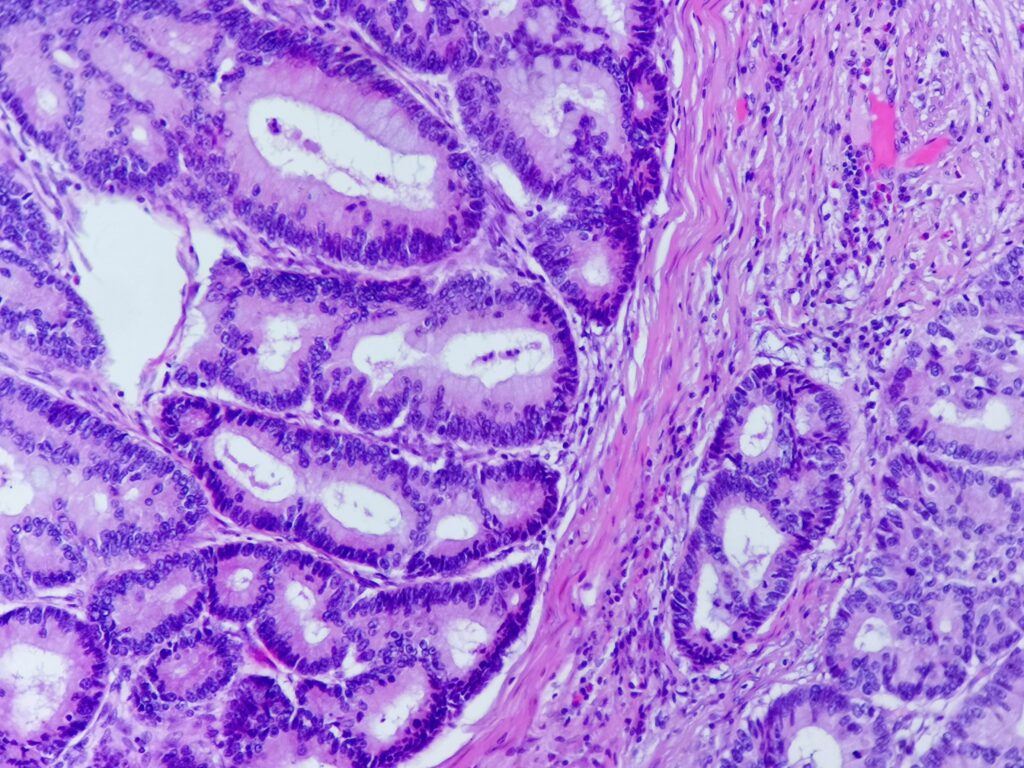

Obrazy mikroskopowe: